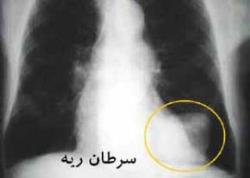

سرطانهايي كه با مصرف سيگار ايجاد ميشود

سرطانهاي ريه، حنجره، مري، كليه ـ پانكراس و معده با سيگار ارتباط مستقيم دارند كه البته در اين بين، 2 سرطان اول عمدتا در سيگاريها ديده ميشود و در افراد غير سيگاري خيلي نامحتمل هستند.